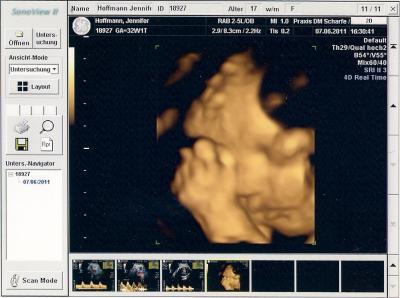

soo war ja dienstag beim frauenarzt da hat sie wieder 20 minuten ctg gemacht da war alles unauffällig. urin war in ordnung. dann hat sie nochmal ultraschall gemacht weil ja meine kleine ja immer ein bisschen kleiner war. Sie hat in zwei wochen auch nur 90gramm zugenommen und wiegt jezt 1410gramm in der 33.ssw und laut entwicklung entspricht das einer 30.ssw. Sie meinte das das unterste grenze ist und hat auch noch mal nach der durchblutung geschaut aber da war alles in ordnung. was meint ihr ist das noch okey mit dem gewicht oder ist das schon dolle wenig??? soo und hier noch mal ein bildchen von meiner kleinen

Bild zu zurück vom frauenarzt - Forum für August - Mamis

Also dafür dass deine Maus auf der unteren Perzentile ist, ist sieht sie auf dem 3D ganz schön propper aus! :-) hat ja schon richtige Pausbäckchen! :-) Und wenn deine Ärztin zum Gewicht nix weiter gesagt hat und auch sonst alles ok ist, würde ich mich jetzt nicht verrückt machen, wobei es nicht wirklich viel ist vom Gewicht, da geb ich dir recht. Aber du weißt ja auch dass das nur Schätzwerte sind!! Alles Gute! LG